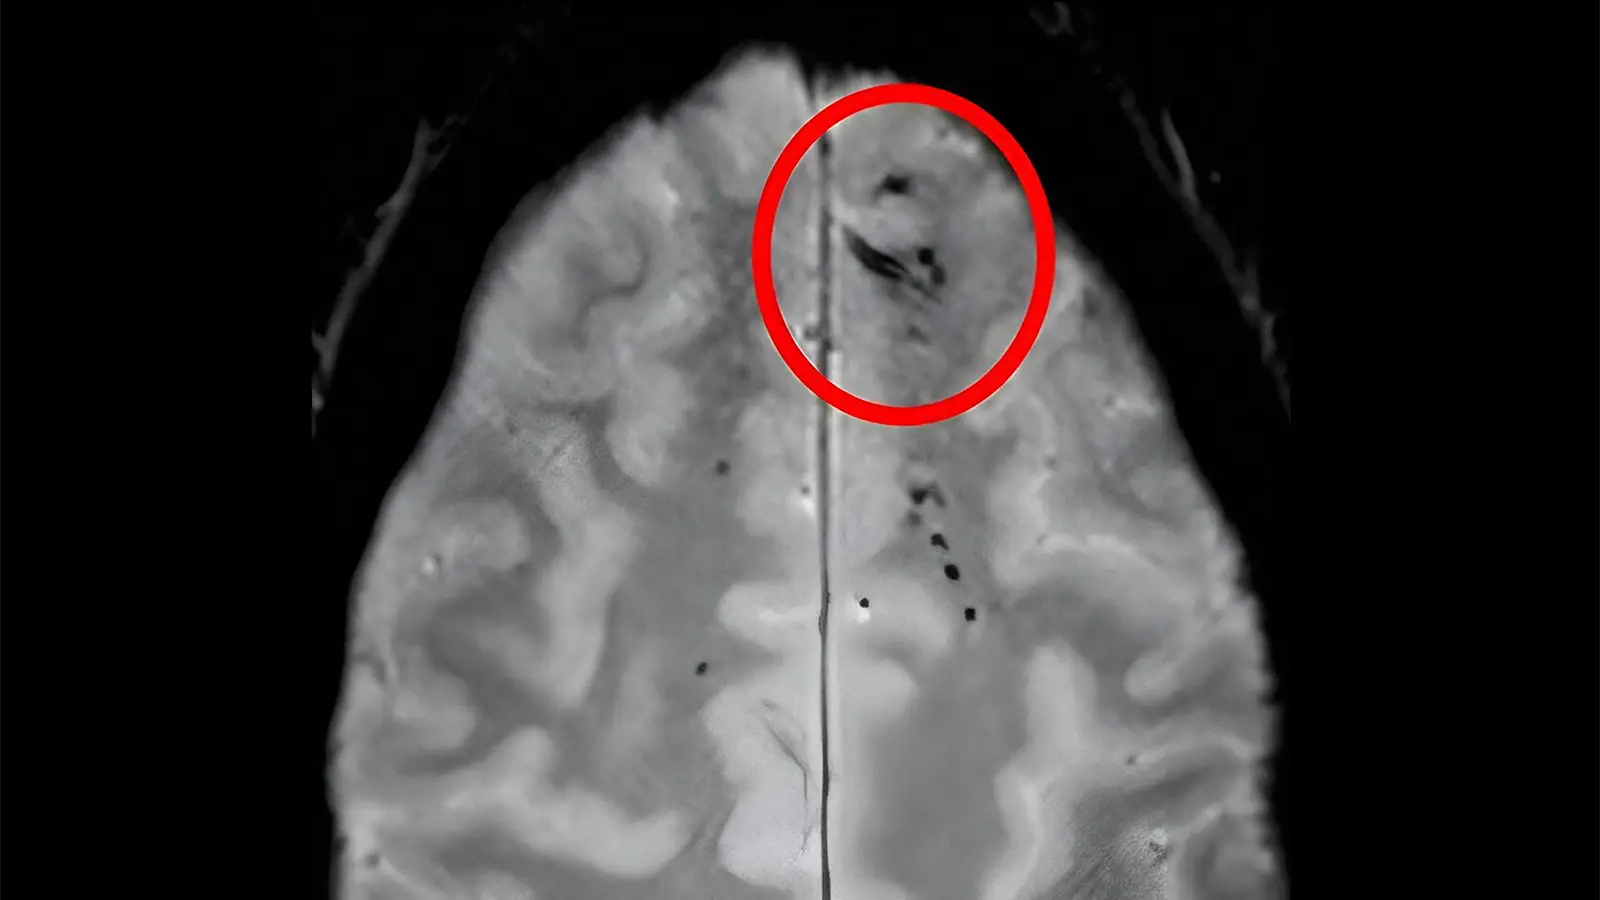

The location and amount of brain microbleeds that a person has could be telling of their risk of dementia, according to an observational analysis.

Cerebral microbleeds, the neuroimaging findings of small blood product deposits, can be considered a sign of cerebral small vessel disease and have previously been associated with dementia and subsequent stroke. Regarding specific microbleed patterns, prior work suggests that microbleeds in the lobar regions and cortical superficial siderosis are consistent with cerebral amyloid angiopathy (CAA), whereas subcortical microbleeds indicate a hypertensive cause.

Participants meeting study criteria came out to 1,583 older adults (mean age 76 years), of whom 22.8% had cerebral microbleeds detected on MRI.